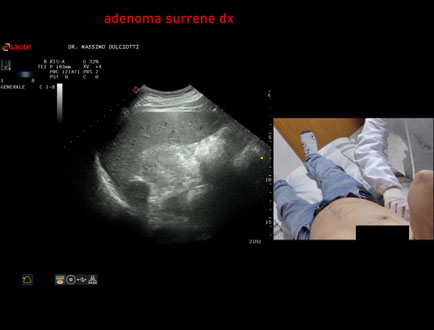

Data inserimento: 17/03/2025

Ecografia del: 05/03/2025

Strumento: Samsung

Sonda: Convex

Età Paziente:

Commento all'esame: adenoma surrenalico sn.

Conclusioni: adenoma surrenalico sinistro (left adrenal adenoma).

Realizzazione: Dr. F. Pietro Tarini - Gubbio (PG)

Presentazione: Dr. Massimo Dolciotti - Ancona

Elaborazione digitale: Andrea Dini - Ancona